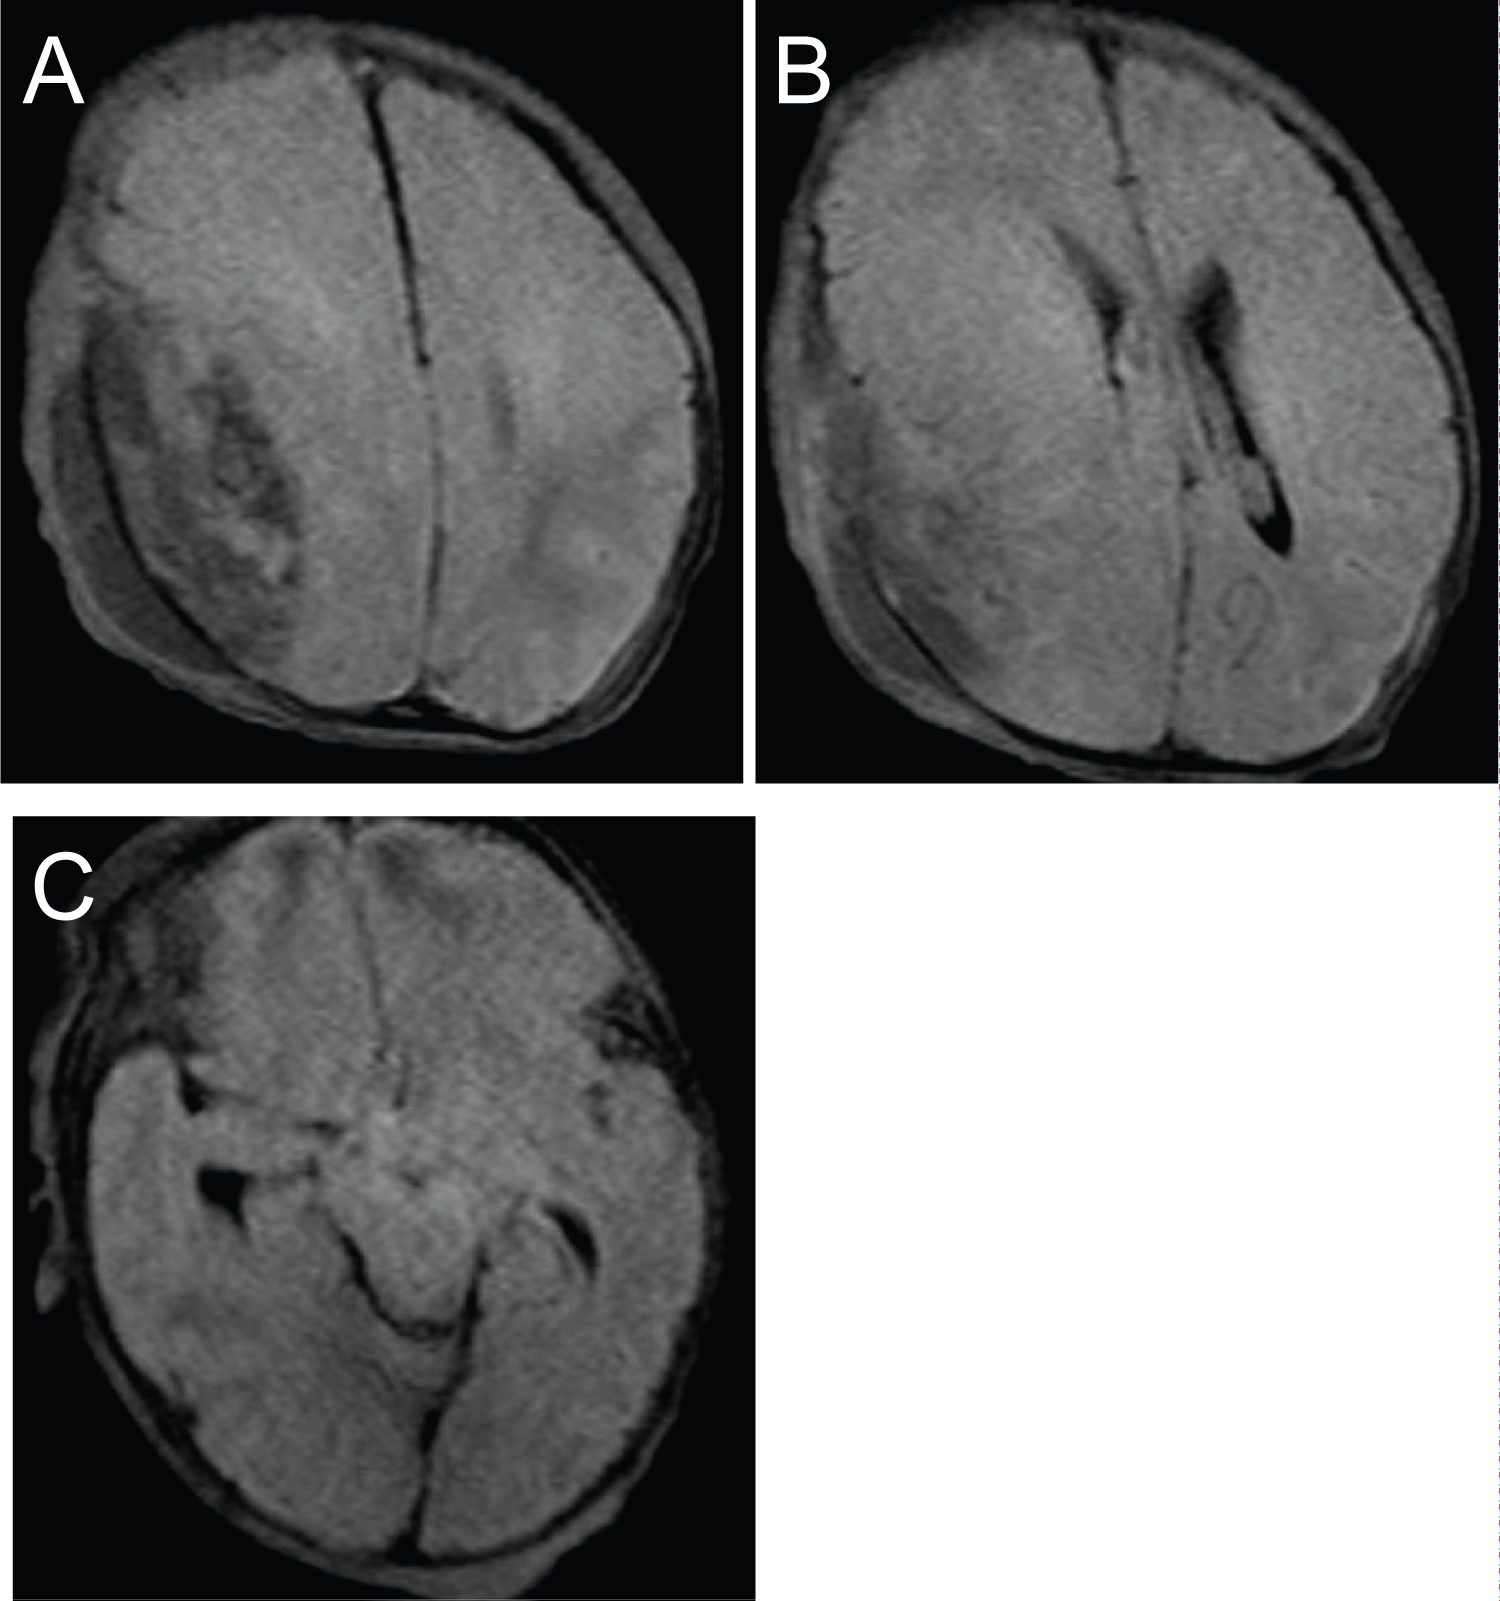

An initial head ultrasound (Figure 1) suggested the possibility of an epidural or subdural hematoma. Subsequent brain CT scans (Figure 2) revealed a large right-sided parietal EDH with a maximum thickness of 1.8 cm, diffuse subarachnoid blood, effacement of the right lateral ventricle, and a 4 mm midline shift. A CT scan of the bony window (Figure 2) uncovered a complex right parietal skull fracture with a 3 mm inwardly displaced depression of the fracture.

Figure 1: Transfontanellar ultrasound demonstrating intracranial bleed. (A) Coronal view; (B) Transverse view. View Figure 1

Neurology was consulted to facilitate continuous EEG monitoring. To better characterize the extent of the intracranial hemorrhage and limit radiation exposure, a Half-Fourier Acquisition Single-shot Turbo Spin Echo Magnetic Resonance Imaging (HASTE MRI) of the brain was performed. The results showed an expanded EDH, a 5 mm midline shift, and a trapped right ventricle (Figure 3). A repeat hematocrit returned at 32%.

Figure 3: Pre-operative MRI brain HASTE protocol presented in T1 STIR. (A) Right parietal epidural hematoma, slightly increased in size from previous, with resultant mass effect on the right temporal and parietal lobes; (B) Trapped right ventricle with 5 mm midline shift; (B, C) Reduced diffusion along the bilateral temporal and parietal lobes with signal characteristics suggestive of subarachnoid hemorrhage. View Figure 3